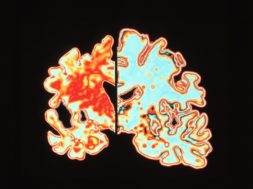

Η ακριβής αιτία της νόσου του Alzheimer δεν είναι γνωστή. Όπως γνωρίζετε, προκαλεί απώλεια μνήμης και παρακμή της γνωστικής λειτουργίας. Αν γνωρίζετε κάποιον που πάσχει από αυτή τη φρικτή ασθένεια, ξέρετε πόσο βάναυση είναι. Δεν υπάρχει θεραπεία … ακόμα. Ωστόσο ένα νέο εμβόλιο που εισέρχεται τώρα στην «Τρίτη Δοκιμαστική Φάση» φαίνεται πολύ ελπιδοφόρο.

Επί του παρόντος, δεν μπορείτε να πάτε στο γιατρό και να ζητήσετε να πάρετε το εμβόλιο. Ωστόσο, δεν πρέπει να εκπλαγείτε αν συμβεί νωρίτερα από ό, τι ελπίζατε ποτέ. Οι ερευνητές πιστεύουν ότι οι ασθενείς με Alzheimer έχουν πλάκες που περιέχουν β-αμυλοειδές, μια κολλώδη εγκεφαλική πρωτεΐνη που σχηματίζεται στον εγκέφαλο.